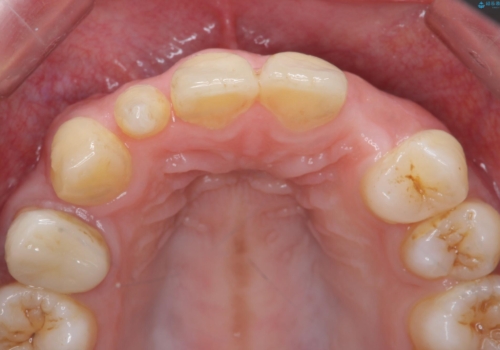

前歯の審美的なブリッジ (歯列矯正後)

- 歯列矯正後に前歯にブリッジを入れた方の経過です。

矯正治療で歯の位置を整えてからブリッジを入れると歯の幅を自由に設定できるため、左右対称にできます。結果矯正なしでいきなりセラミックにする場合と異なり、無理に角度を変えたりする必要がなく、神経をなるべく温存したまま審美的なセラミック治療が行えます。